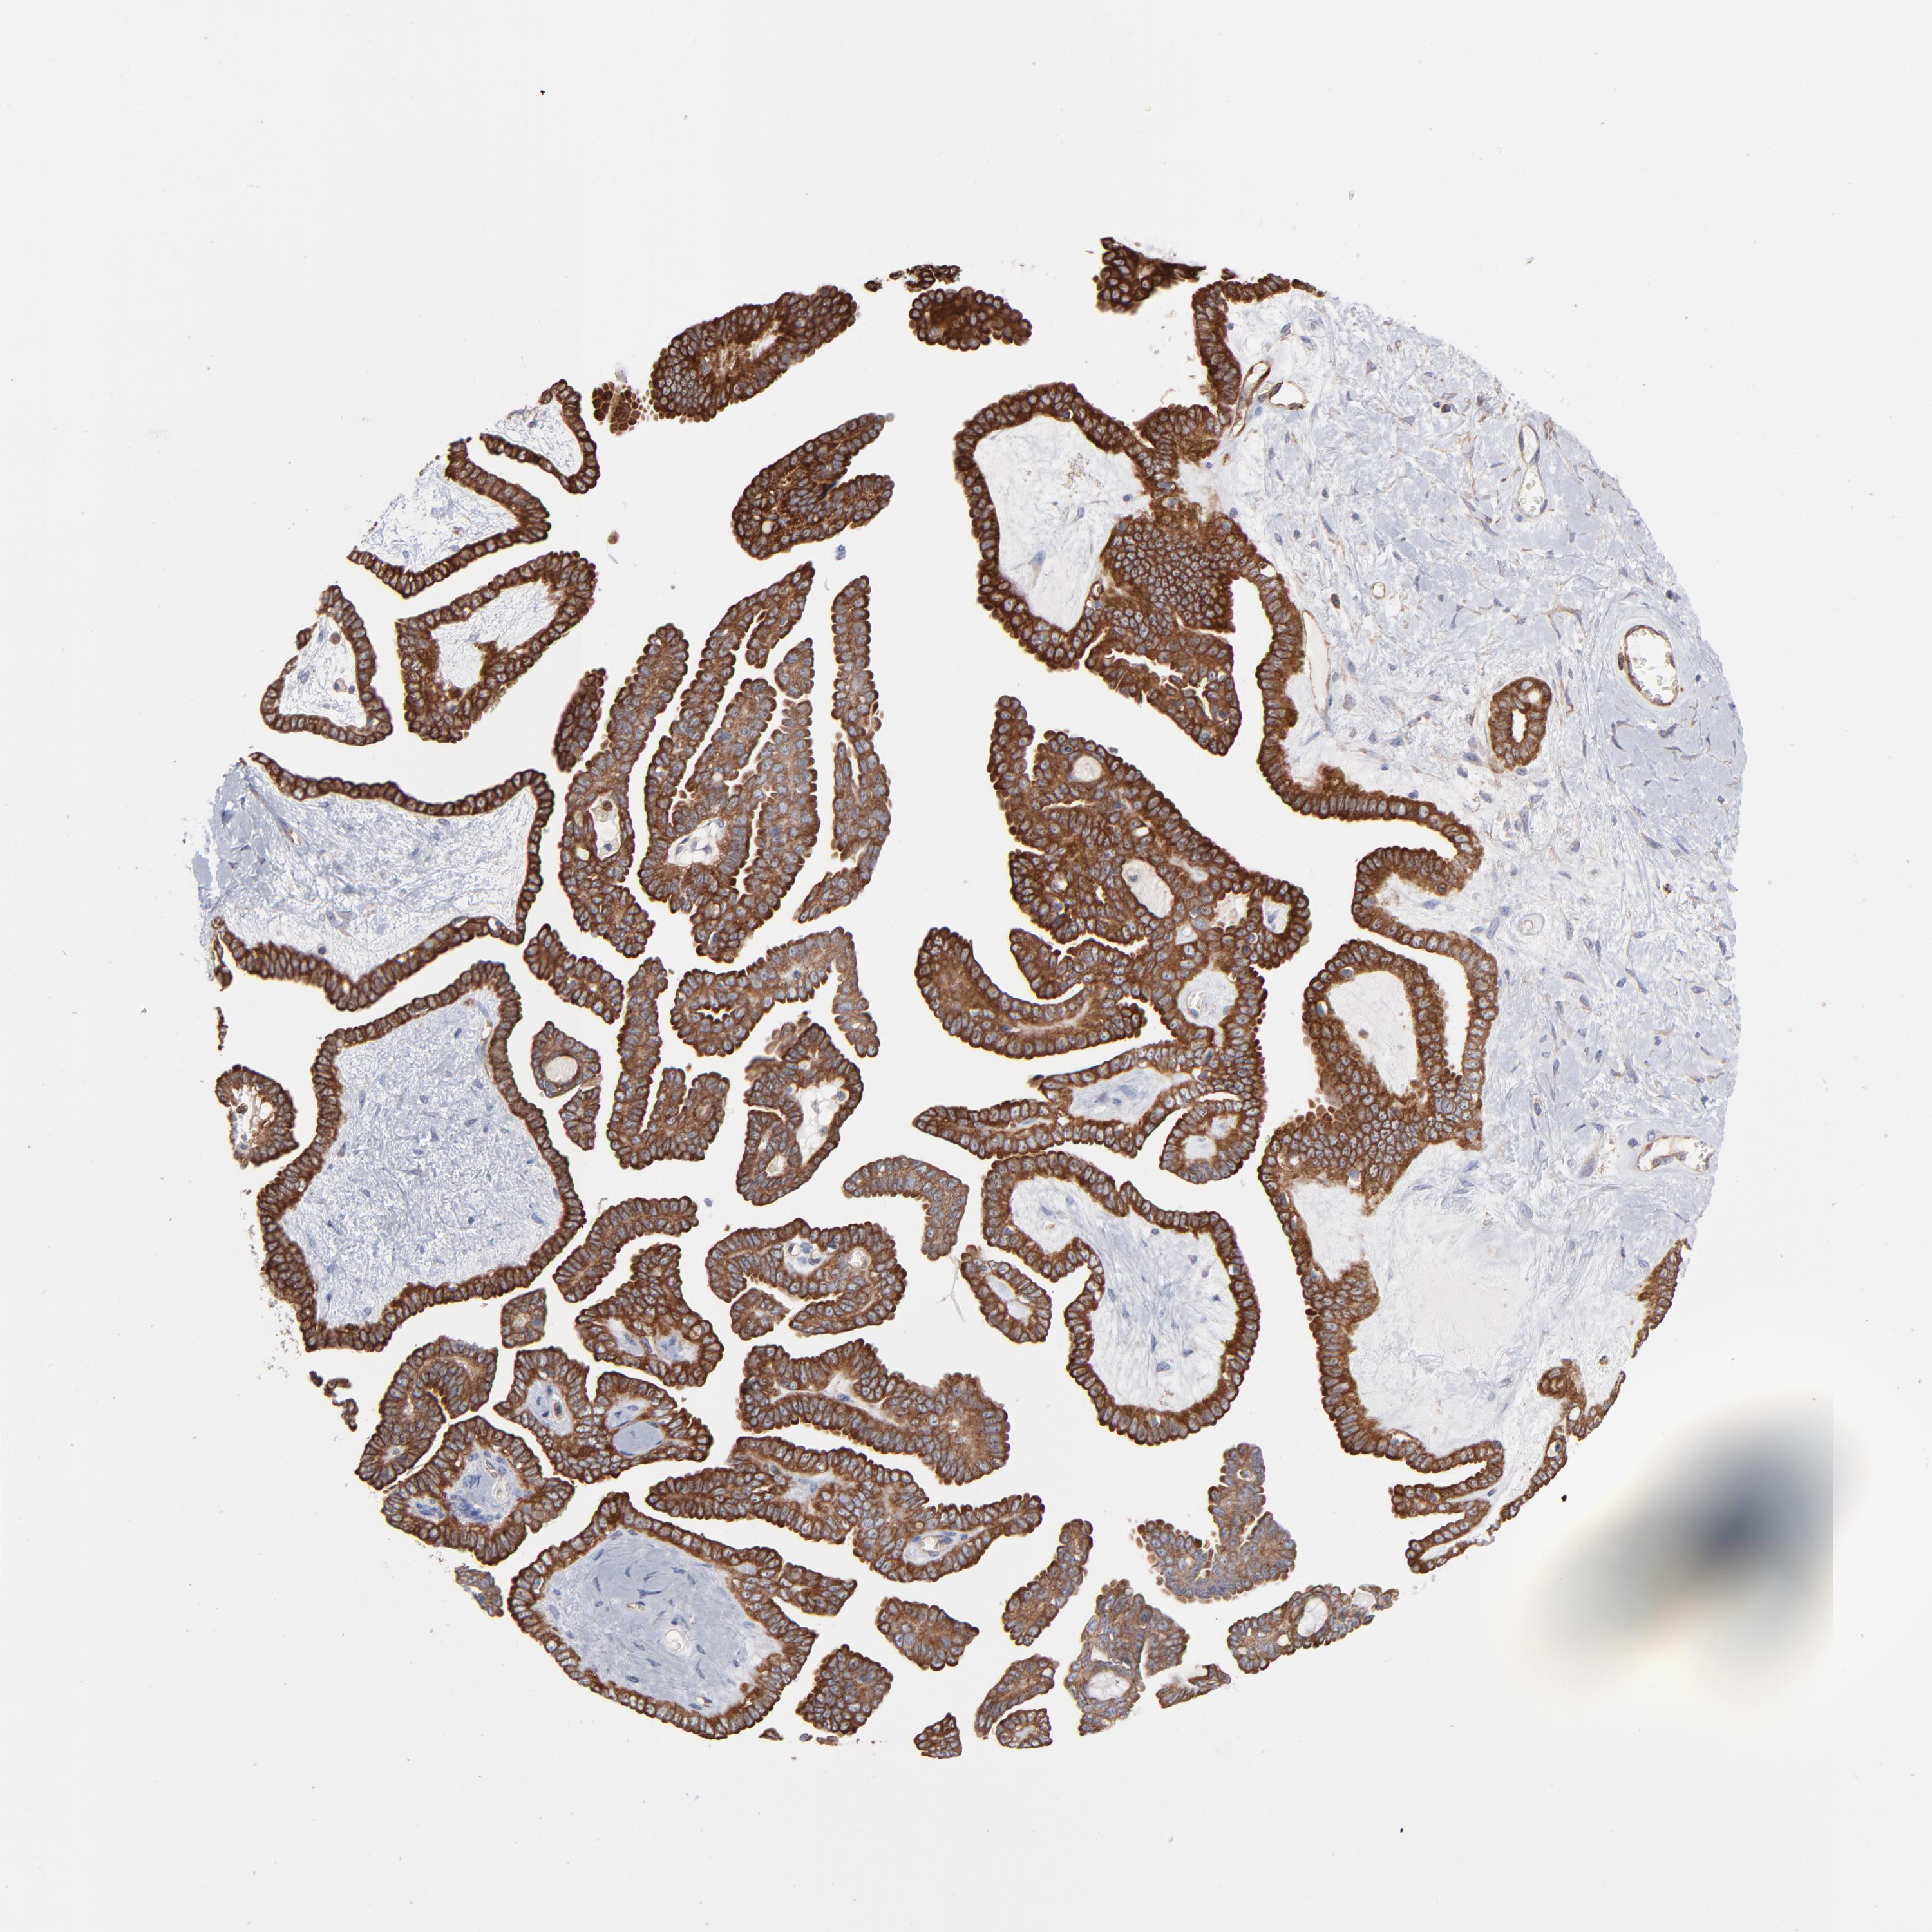

OVARIAN CANCER - Protein expressioni

A mouse-over function shows sample information and annotation data. Click on an image to view it in a full screen mode. Samples can be filtered based on level of antibody staining by selecting one or several of the following categories: high, medium, low and not detected. The assay and annotation is described here.

Note that samples used for immunohistochemistry by the Human Protein Atlas do not correspond to samples in the TCGA dataset.

Antibody stainingi

Antibody staining in the annotated cell types in the current human tissue is reported as not detected, low, medium, or high, based on conventional immunohistochemistry profiling in selected tissues. This score is based on the combination of the staining intensity and fraction of stained cells.

Each image is clickable and will lead to virtual microscopy that enables deeper exploration of all samples and also displays staining intensity scores, fraction scores and subcellular localization as well as patient and tissue information for each sample.

Antibody CAB003841

Staining

High

Medium

Low

Not detected

Intensity

Strong

Moderate

Weak

Negative

Quantity

>75%

75%-25%

<25%

None

Location

Nuclear

Cytoplasmic/membranous

Cytoplasmic/membranous,nuclear

Cystadenocarcinoma, mucinous, NOS

Carcinoma, endometroid

Cystadenocarcinoma, serous, NOS